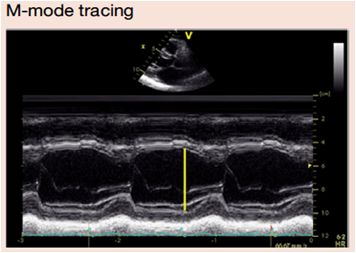

1、M型超声心动图

➤ 1.1 左心室测量(内径)

左室胸骨旁长轴切面

1、可重复;

2、时间分辨率高;

3、文献发表数据多;

4、声束方向不垂直,误差大;

5、一维,仅代表形态正常的左室内径。